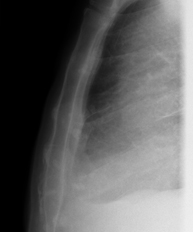

- Chest X-ray

This technique uses X-ray rendered imaging for examining the thoracic cavity (heart, lungs, costal arches, clavicles, etc.).

A chest X-ray uses a small dose of radiation to obtain a two-dimensional image of the thoracic cavity and its contents (lungs, heart, mediastinum, etc.). It is one of the most commonly performed medical tests.